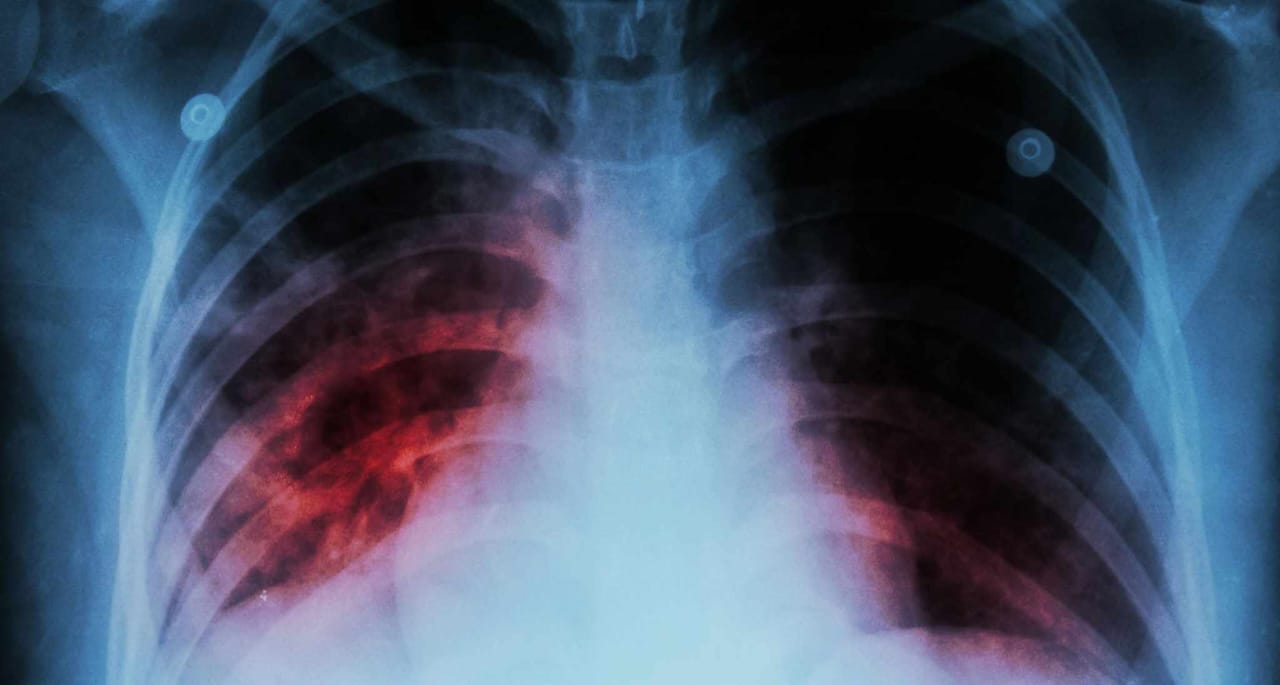

وفي هذا الصدد، أكد الطيب حمضي، طبيب وباحث في السياسات والنظم الصحية، خطورة داء السل، موردا أنه مرض قاتل ويصيب ما يقارب 96 شخصا يوميا في المغرب.

وأضاف حمضي في تصريح له لناظور سيتي، أن هذا الداء يودي بحياة تسع أشخاص يوميا في المغرب.

وحسب الباحث، فإن 15 في المئة من الحالات التي تصاب سنويا بهذا المرض، لا يتم اكتشافها ولا يتم تشخيصها، مثلما أن ثلثا حالات السل المقاوم للأدوية لا يتم تشخيصها، وهو ما يؤدي إلى حدوث مشكلة صحية عمومية وصفها بالخطيرة تتمثل في انتشار السل المقاوم للأدوية، يردف الباحث في السياسات والنظم الصحية.

وذكر المصدر، أن جهة طنجة تطوان الحسيمة، والرباط وسلا والقنيطرة وكذا الدار البيضاء وسطات، تعد من الجهات الأكثر تضررا من حيث عدد الإصابات.

وخلص الطبيب، إلى أنه يتعين للحد من تفشي الداء، أن يتم العمل على التوسع في استخدام اختبارات التشخيص السريع لتشخيص مرض السل بشكل سريع ومبكر والحد من انتشار الداء، مشددا على ان الدولة مسؤولة بشكل كامل على مواجهة المرض من خلال تأمينها لحق العلاج للأفراد وضمان سلامة المجتمع.